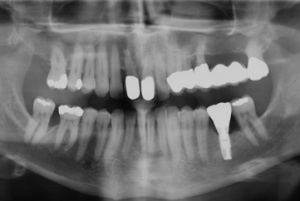

Mit der Transplantation eines freien Schleimhauttransplantats im Januar 2001 konnte die aktive parodontologische Therapie abgeschlossen werden, der Patient wurde zur Unterstützenden Parodontitistherapie in das Recallsystem der FU VIIa aufgenommen. Der Patient stellte sich dabei halbjährlich zur Durchführung von professionellen Zahnreinigungen vor, die durch die bereits beschriebenen Elemente der Erhaltungstherapie ergänzt wurden. Ein wichtiges Element der Erhaltungstherapie ist die regelmäßige parodontale Diagnostik mit der Erstellung eines Parodontalstatus, um gegebenenfalls Rezidive frühzeitig erkennen und behandeln zu können. Im Jahre 2006 kam es an einzelnen Zähnen zu Rezidiven, es konnten Sondiertiefen von bis zu 7mm sondiert werden. Es wurde daher ein Scaling/Rootplaning der rezidivierenden Taschen durchgeführt, an einzelnen Zähnen erfolgten im Jahre 2008 zudem weiterführende parodontalchirurgische Maßnahmen im Sinne von Lappenoperationen (s. Abb. 16). Im Rahmen der unterstützenden Parodontitistherapie erfolgte neben den schon erwähnten halbjährlichen professionellen Zahnreinigungen im November 2012 eine erneute subgingivale Instrumentierung an 21, 24, 28, 41, 46. Die letzte Vorstellung des Patienten erfolgte im April 2015 (s. Abb. 17, 18, 19). Dabei stellte sich die marginale Gingiva entzündungsfrei dar, die approximalen Sondiertiefen betrugen durchschnittlich zwei bis drei Millimeter, geringgradig erhöhte Sondiertiefen verbleiben an 21, 28, 36, 47. Die häusliche Mundhygiene des Patienten stellte sich wie schon über den gesamten Beobachtungszeitraum mit einem API von 30 % als gut dar. Die periimplantären Gewebe zeigten sich bei der Vorstellung im April 2015 unauffällig.